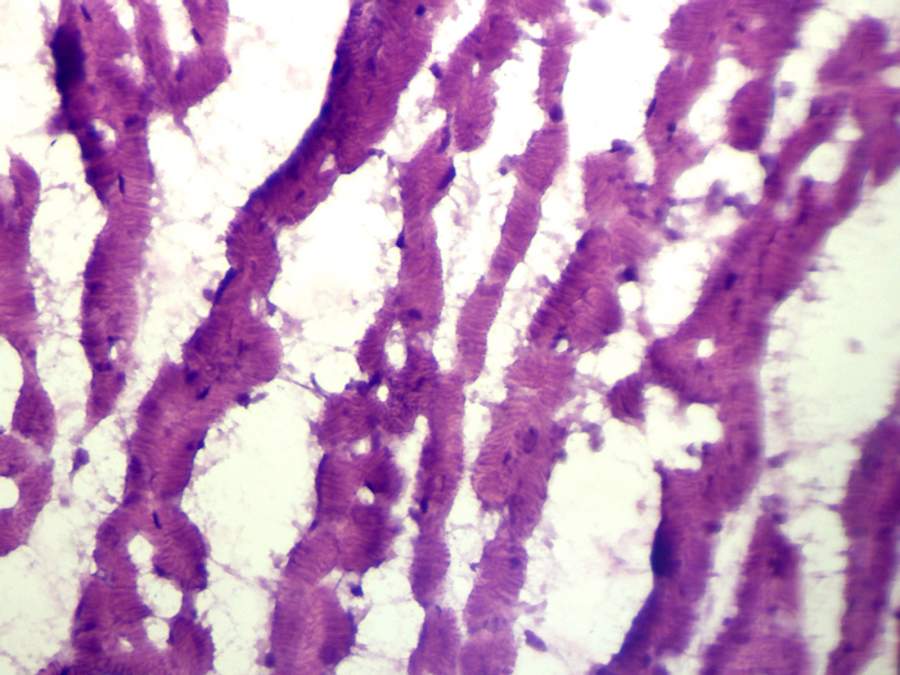

ÇëÄÄλ¸ßÊÖ°ïÎÒ·ÖÎöÒ»ÏÂÕâ7ÕÅÐÄÔà×éÖ¯µÄHEȾɫ±ù¶³ÇÐÆ¬£¬±¾ÈËÍêÈ«²»¿´²»¶®£¬

¸ÕѧÍêÃâÒß×黯£¬°´ÕÕÀÏʦµÄ˵·¨¡£Æ¬×ÓÉÏϸ°û²»ÔÚÍ¬Ò»Æ½Ãæ£¬Ö¤Ã÷ÇÐÆ¬²»¾ùÔÈ£¬»òÕßÇÐÆ¬¹ýºñ¡«ÓÐЩÓм¸ÕÅȾɫ¹ýÉ×îºóÒ»ÕÅΪÀý£©£¬ËÕÄ¾ËØÈ¾µÄÓзÇÌØÒìÐÔȾɫ£¬ÒÀºìÒ²ÊÇ£¬Ï¸°ûÖÊÀïȾɫ̫ºì£¬Ï¸°ûºËȾɫ̫À¶£¨¶¼ºÚÁË£©£¬Ï¸°û×ÅÉ«Óë±³¾°É«Ïà²î²»Ã÷ÏÔ¡£×îÖ÷ÒªµÄÊÇ£¬Ã¿ÕÅÆ¬×Ó¶¼²»ºÏ¸ñ£¬»òÕßÊÇÈ¡ÕÕµÄλÖò»ºÏ¸ñ£¬ÒòΪÇÐÆ¬ÉÏϸ°ûÃ÷ÏÔ²»ÔÚÍ¬Ò»Æ½Ãæ£¬°´ÕÕÀÏʦ˵·¨£¬ÕâÖÖÆ¬×Ó²»ºÏ¸ñ£¬ÊDz»»á·¢¸øÆäËûʵÑéÊҵġ£ ·¢×ÔСľ³æAndroid¿Í»§¶Ë |